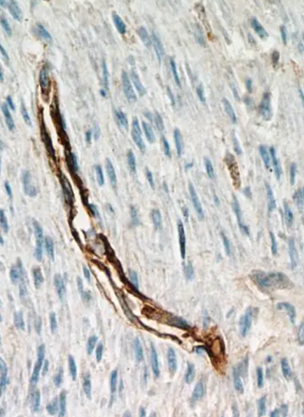

CD34+ 干細胞是一類重要的多能祖細胞,主要存在于骨髓、外周血和臍帶血中,具有自我更新和分化為多種細胞類型的潛力。它們在造血系統、血管生成和組織修復中發揮關鍵作用,并可能參與肝臟、心臟等器官的再生。

CD34 是一種細胞表面糖蛋白,屬于唾液黏蛋白家族,參與細胞間黏附、遷移和信號傳導,主要表達于造血干細胞/祖細胞(HSPCs) 、血管內皮祖細胞(EPCs)和某些間充質干細胞(MSCs)亞群,可來源于不同組織。

CD34+ 干細胞具有多譜系分化能力,可生成多種細胞類型,包含造血分化系統和非造血分化系統(爭議性)。前者可進一步分化為髓系細胞(粒細胞、單核細胞、巨噬細胞)、淋巴系細胞(T細胞、B細胞、NK細胞)和紅細胞及血小板;后者是近年研究發現,CD34+ 細胞在特定條件下可能分化為肝細胞樣細胞(HLCs)、血管內皮細胞、心肌樣細胞和神經樣細胞,但非造血分化效率較低,且機制尚不明確,需進一步驗證。目前,CD34+干細胞常應用于造血干細胞移植、血管再生治療、肝臟再生研究和組織工程與再生醫學等方面,其分離方法通常為免疫磁珠分選(MACS)和流式細胞分選(FACS)兩種,其中免疫磁珠分選為常用的分離方法。